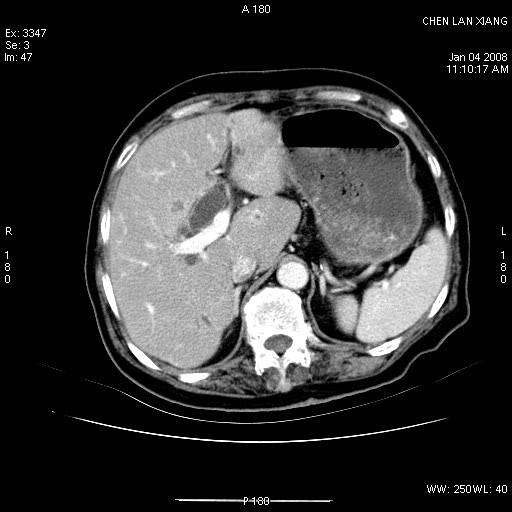

女,76岁,腹痛3-4天,b超示:肝内实性肿物,胆囊强回声,胆总管扩张.

考虑:1、胆总管下端结石伴梗阻性肝内外胆管扩张(肝左叶外侧段肝内胆管多发结石、胆管炎);

2、肿囊癌累及肝,不除外 黄色肉芽肿性胆囊炎。

1 胆总管末端结石伴肝内胆管结石,肝内外胆管扩张。2 胆囊扩大,胆囊壁不规则增厚,内见软组织密度影。考虑:慢性胆囊炎,不除外胆囊癌!

标题: 肝右叶病灶

胆囊癌侵犯肝右叶?

1)胆囊癌伴肝脏转移。2)胆总管下端结石、肝内胆管结石伴肝内外胆管扩张。